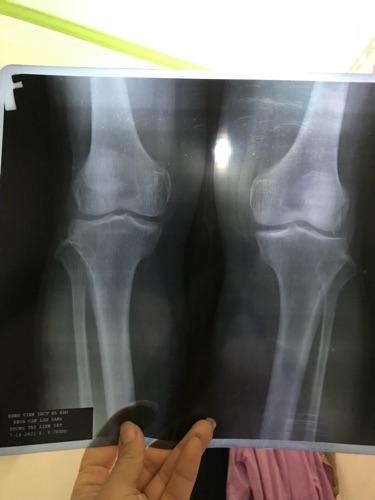

Thưa các bác sỹ mẹ e bị tràn dịch khớp gối đã đi viện và uống thuốc, tiên trực tiếp vào gối mấy lần mac chưa khỏi. Các bác tư vấn xem mẹ e co thể uống thuốc hay điều trị phương án nào ạ

Chào bác , bác gửi hình ảnh phim XQ và siêu âm để các BS tư vấn thêm bác nhé